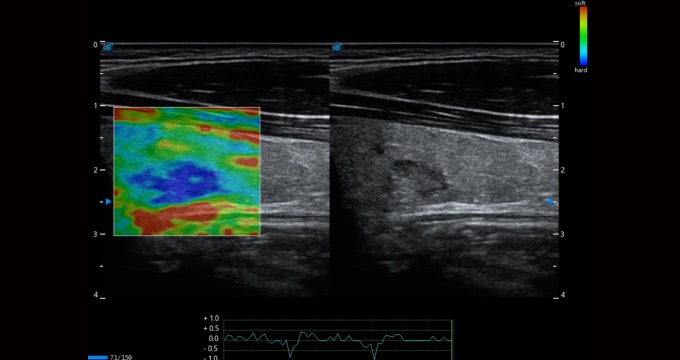

彈性成像支持多把探頭,滿(mǎn)足全面的臨床應(yīng)用。無(wú)需高頻度外力作用可真實(shí)反映組織的形變,具有良好的重復(fù)性,幫助醫(yī)生早期洞察潛在的病理學(xué)特征。